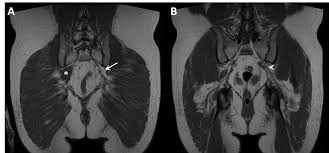

The Radiology Assistant Perianal Fistulas

The Radiology Assistant Perianal Fistulas from radiologyassistant.nl

The video covers the most. Hint you are sitting on it right now. The pelvic girdle consists of two symmetrical halves. The muscles of the pelvis form its floor. Hepatocellular carcinoma or liver cancer. Furthermore, the pelvis protects the pelvic and abdominopelvic viscera. (2) the levator ani and the coccygeus, which together form the pelvic diaphragm and are. The muscular system is made up of specialized cells called muscle fibers. • describe the bony anatomy of the pelvic floor • describe the skeletal muscle of the pelvic floor • discuss the arterial supply to pelvis. Abdominal and pelvic anatomy encompasses the anatomy of all structures of the abdominal and pelvic cavities. 3 enumerate the muscles of true pelvis. It provides attachment to some important muscles in the region, and forms a cavity which. 13 what portion of the bony pelvis is the arrow pointing to?

Functional anatomy of the male. Related online courses on physioplus. 13 what portion of the bony pelvis is the arrow pointing to? (1) the obturator internus and the piriformis, which are muscles of the lower extremity, and will be described with these (pages 476 and 477); • describe the bony anatomy of the pelvic floor • describe the skeletal muscle of the pelvic floor • discuss the arterial supply to pelvis. • to assess equivocal imaging findings • staging of hepatic neoplasms • metastatic workup of primary malignancies • diagnosis of abdominal masses • assessment of biliary problems • diagnosis of vascular lesions. Pelvic examinations are common in clinical cases of obstetrics and gynecology the bony pelvis can be divided and viewed into 2 parts: N patient preparation n patient position n scanogram.